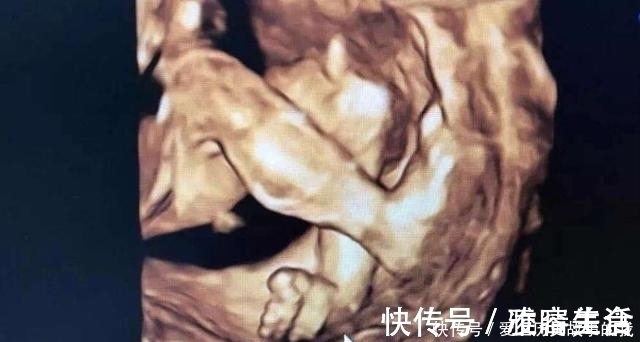

四维检查是对胎儿的各项器官进行排畸筛查,医生通过彩超仪器来观察胎儿的发育情况、胎盘、羊水等,还可以打印出比较清晰的胎儿面部图片,孕妈可以看到腹中孩子的大致长相。很多宝爸宝妈第一次看到宝宝如此清晰的照片,很激动,也顾不上看产检单上的其他数据,就只盯着照片看。其实,四维产检单出来之后,除了看宝宝的照片,其他数据一样要仔细看看。

【 发育|四维彩超,孕妈们最期待的产检,除了看宝宝的照片还需要看什么?】四维彩超是可以比较清晰的看到孩子的四肢和颜面部的发育情况的,如果孩子有兔唇四肢畸形是可以发现的。